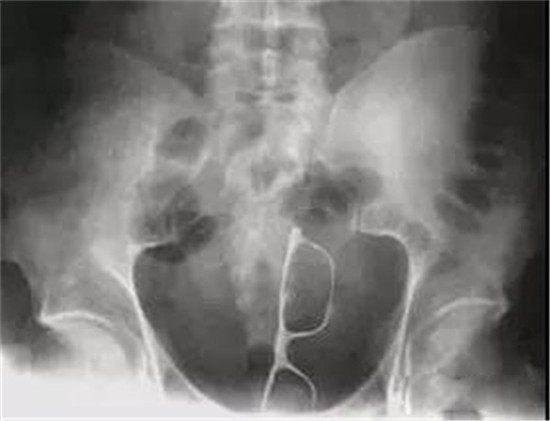

可怜的眼镜。

这玩意大家认识吧,这个东西塞进去,还真不多的。是不是主人想要大肠做文艺青年呢?